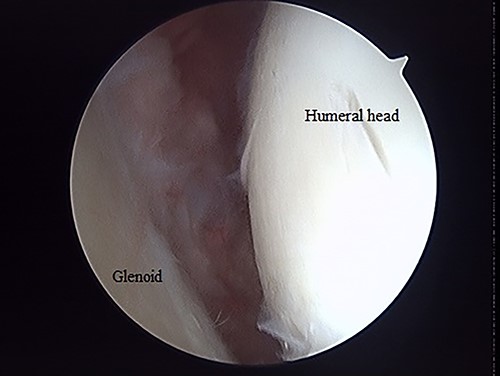

The operation was performed under general anesthesia with an ultrasound-guided brachial plexus block in the beach chair position. First, we performed intra-articular observation by arthroscopy with a 30° scope. Through a posterior portal, we confirmed incongruence of the articular surface of the humeral head, similar to the preoperative findings in 3D-CT (Fig. 4). On the other hand, the posterior joint labrum and glenoid rim were intact. After evaluating the intra-articular lesion, we performed arthroscopic reduction for the impression fracture at the humeral head via the arthroscopic method [5,6]. We split the deltoid muscle and exposed the lateral surface of the humerus. We inserted a Kirschner wire as a reduction guide 2 cm distal from the upper border of the greater tuberosity and 2 cm behind the bicipital groove (Fig. 5). Kirschner wire was inserted to exit the impression lesion while checking the articular surface with an arthroscope (Fig. 6). We created a cortical window (approximately 10 × 10 mm) using a cannulated drill with the Kirschner wire as a guide. To reduce the impression, we pushed the back of the impression using the flat side of the canulated cancellous screw (CCS) drill. After the reduction, artificial bone was inserted from the cortical window to the subchondral bone region to provide support for the depressed area. We then performed a procedure to insert a support screw into the articular surface. The deltopectoral approach was used. First, we dissected the subacromial bursa entirely while visualizing the conjoint tendon. Next, we detached the long head of the biceps at the bicipital groove and sutured it to the pectoralis major muscle. Two CCSs were inserted from the bicipital groove to under the repaired humeral head as support for the reduction site. Finally, after arthroscopic reduction, we performed ORIF for surgical neck fracture using a PHILOS Plate™ (DePuy Synthes).

Posterior arthroscopy of the right shoulder joint. The right is the humeral head side, and the left is the glenoid side. Impression of the humeral head was noted, but the posterior labrum was not damaged.

Posterior arthroscopy of the right shoulder joint showing a reduced depressed surface and the Kirschner wire for reduction guide.